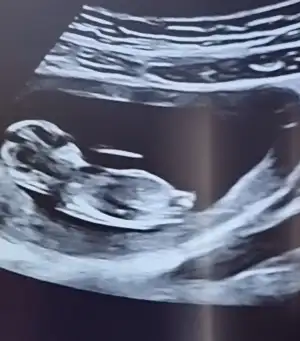

Anladım sanırım o dqer bacaqının qörüntüsü 3 hafta sonra kesin belli olacaqını düşünüoruz 16 haftalık olucak ozman söylerim cinsiyetni inş nasipseÇok karanlık emin olamadım ama tahminim var Erkek sanki

Üstte çizdim orası bacak gibi görünmedi okla gösterdiğim yer nub gibiAnladım sanırım o dqer bacaqının qörüntüsü 3 hafta sonra kesin belli olacaqını düşünüoruz 16 haftalık olucak ozman söylerim cinsiyetni inş nasipse

Çok net erkek .11 12 haftalık nub kız görünüyor du. Sonra yükseldi galiba. 12 +5 e kadar güven vermiyor nubYaa 11 hafta yanitti demekki çok paralel görünüyor du varmı 13 hafta bakmak isterim![]()

Tekrar USG paylaşın demiştiniz 12+5 günlük burada doktor bir tahmin yapmadı ne düşünüyorsunuz :)Ikra meyra